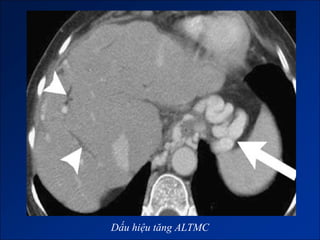

Dấu hiệu tăng ALTMC

2. Dấu hiệu tăng ALTMC